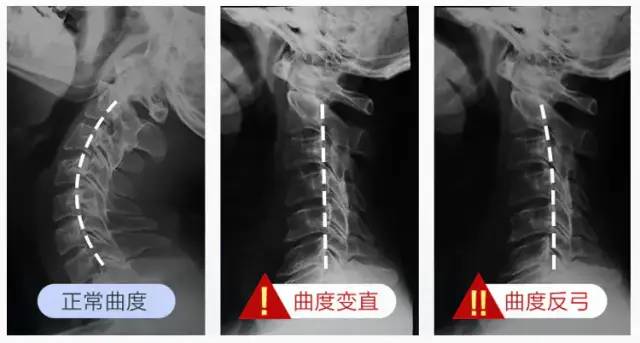

正常生理曲度 颈椎曲度变直 颈椎反弓 信息阅读欣赏 信息村 K0w0m Com

颈椎曲度反弓是什么 工作

颈椎反弓 成因 相关病症 社会关注 历史版本2 快懂百科